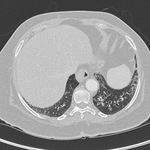

Bronquiectasia

Brônquios com muco retido em uma mulher de 36 anos de idade com aspergilose broncopulmonar alérgica

De Pamela J. McShane, MD; uso autorizado